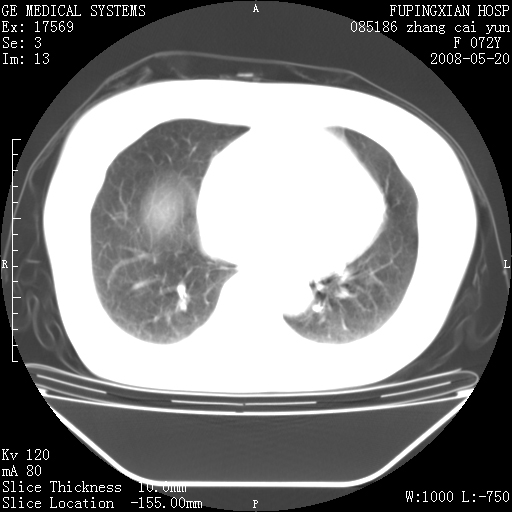

标题: CT13542:发热,咳嗽数日,经抗菌素治疗好转,请大家看排除 [打印本页]

标题: CT13542:发热,咳嗽数日,经抗菌素治疗好转,请大家看排除

有节段性阻塞性肺炎与不张,近段支气管狭窄,周围散在肿大淋巴结影,以周围型肺癌可能性大,建议纤支镜检查。

右肺上叶实变影,内见支气管充气征,右上叶支气管通畅,肺门区未见软组织密度影,抗炎治疗有效,考虑炎症,建议继续抗炎治疗复查。

右肺阻塞性肺炎  不除外支气管内膜结核

考虑为:右肺上叶感染性病变。建议:1)继续抗炎治疗后复查。2)必要时行纤支镜检查。

右上肺实变,间内有支气管充气征,考虑炎症,建议抗炎后复查